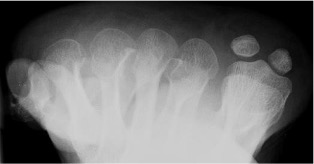

Dorsoplantar view foot (DP)

Radiographic technique

Taken either weightbearing or non-weightbearing with the X-ray beam angled 10° towards the heel (so that it is perpendicular to the metatarsals) and directed to the base of the third metatarsal.

Anatomical review areas

- General-purpose view shows the majority of the foot from the midtarsal area distally

- The neck of the talus, distal calcaneus, tarsus, metatarsals, metatarsophalangeal joints and phalanges clearly seen

- Calcaneo-cuboid and talo-navicular joints making up the midtarsal (Chopart) joint

- Tarso-metatarsal (Lisfranc) joint

- Sesamoid bones seen through the first metatarsal head

- Bodies of talus and calcaneum occluded by superimposition of the distal tibia and fibula